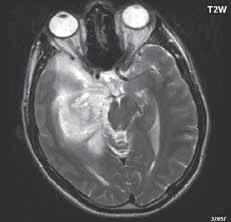

I 2 1 Difuzní astroc ytom low grade

I 2 2

I 2 3

I 2 4

astrocytom